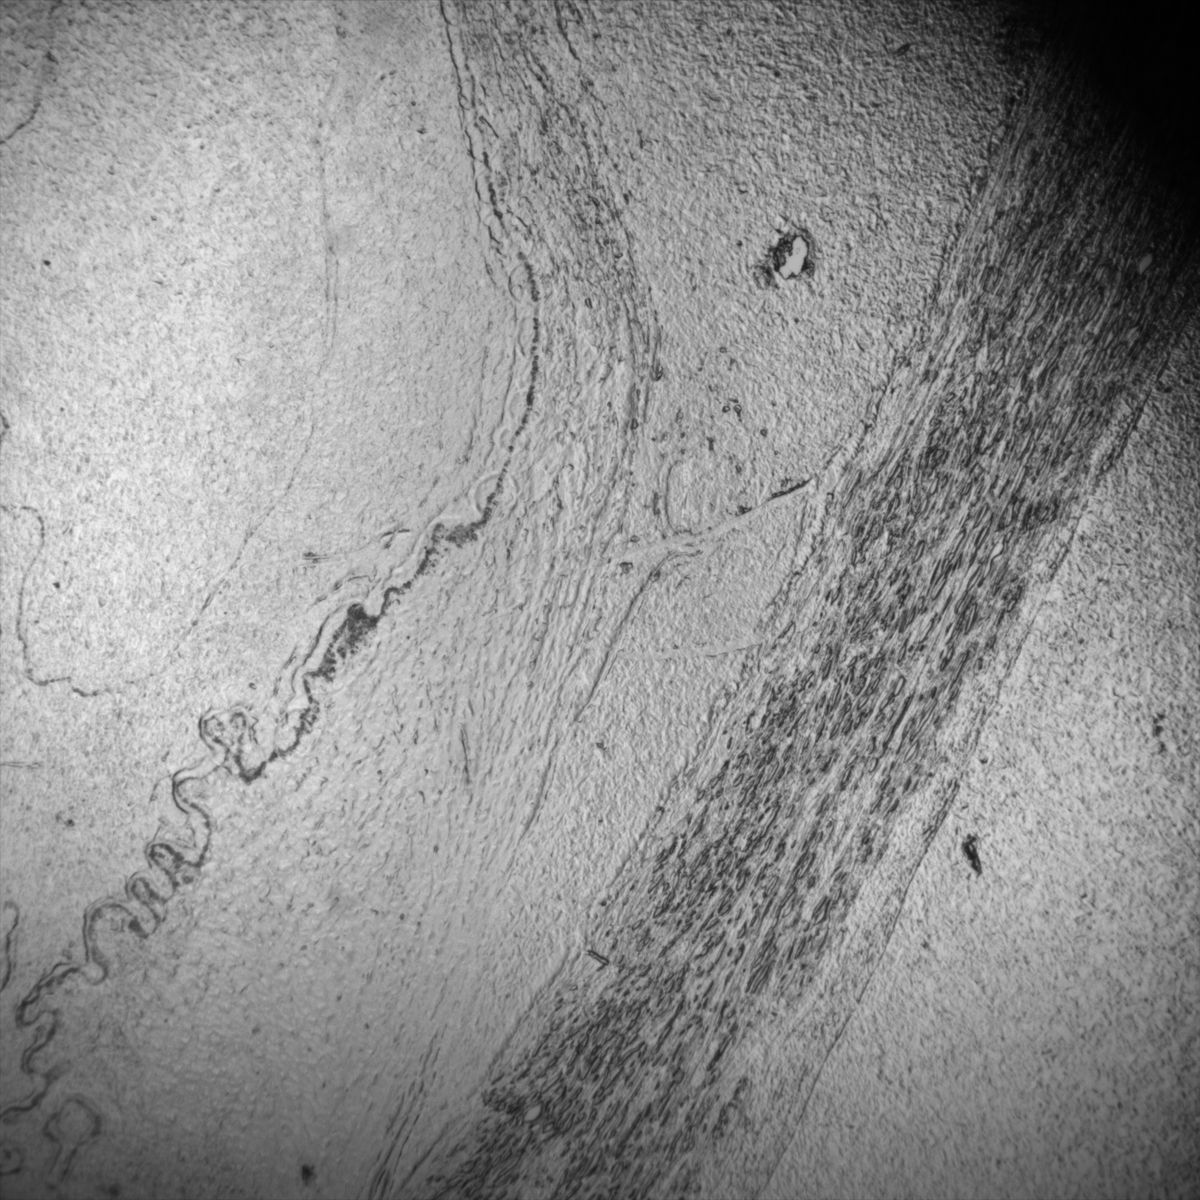

Healthy Eye

Overview 1

Overview 2

Overview 4